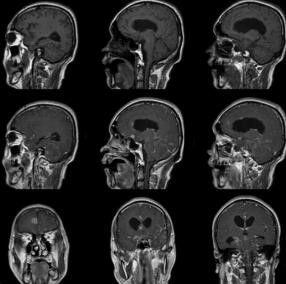

患者男,43岁,外院检查示颅内病变性质待查(图1)。

图1 脑底池结构显示不清,双侧颞叶脑回皮质增厚并呈长T2信号,脑沟增宽。左侧基底节区见斑点状长T1、长T2信号影。弥散加权左侧颞极见斑片状高信号。幕上脑室扩大,尤以右侧为著。中线结构居中。增强:室管膜、中线处脑膜、左侧外侧窝池多发结节样强化影